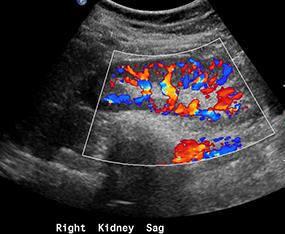

US can also be used to quantitate various bodily processes, such as blood flow. There are several ways to do this. One is to use 'color flow' imaging, which shows movement of fluids like blood either toward or away from the transducer using a scale from blue to red. Another way is to pick a small area of the image and display movement within that region as a graph. The ability to quantitate flow is what makes US so useful in imaging structures like the arteries in the neck and the heart.

This is the same kidney, with color flow imaging. You can see how dramatic the vascularity is within this organ. The color scale does not show arteries as red and veins as blue, but the color differences relate to whether the flow is toward or away from the transducer.